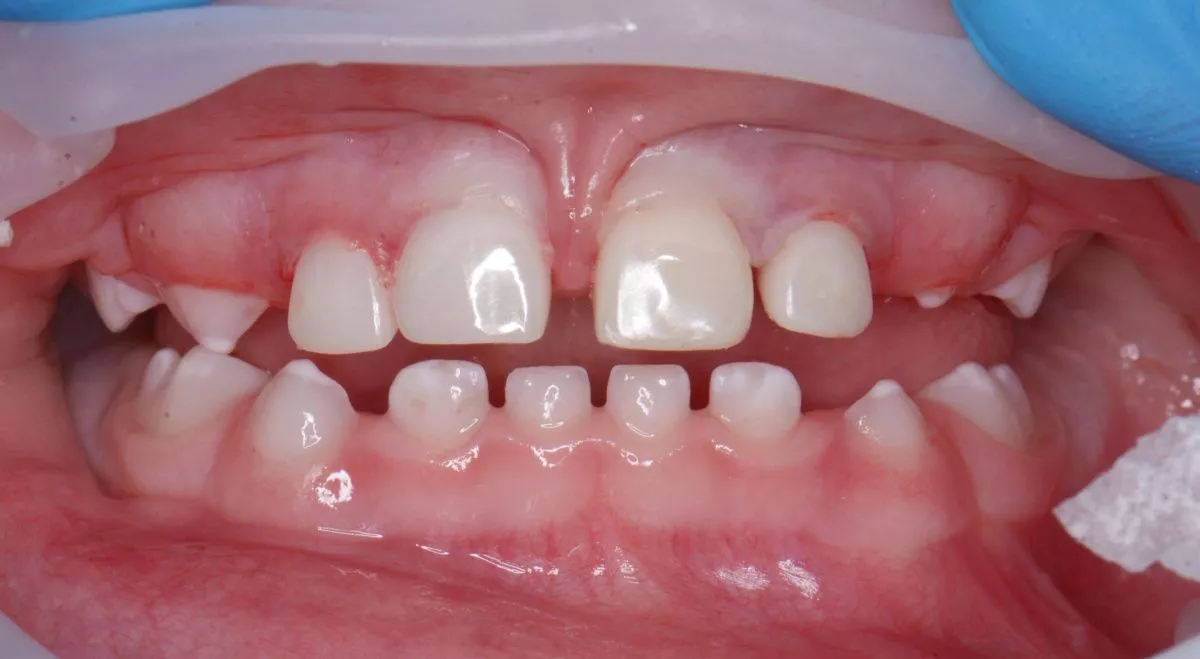

Лечение под наркозом - установка коронок и профессиональная гигиена у детей

етская стоматология лечение под наркозом. Лечение под наркозом - установка коронок и профессиональная гигиена у детей - до процедуры

етская стоматология лечение под наркозом. Лечение под наркозом - установка коронок и профессиональная гигиена у детей - после процедуры